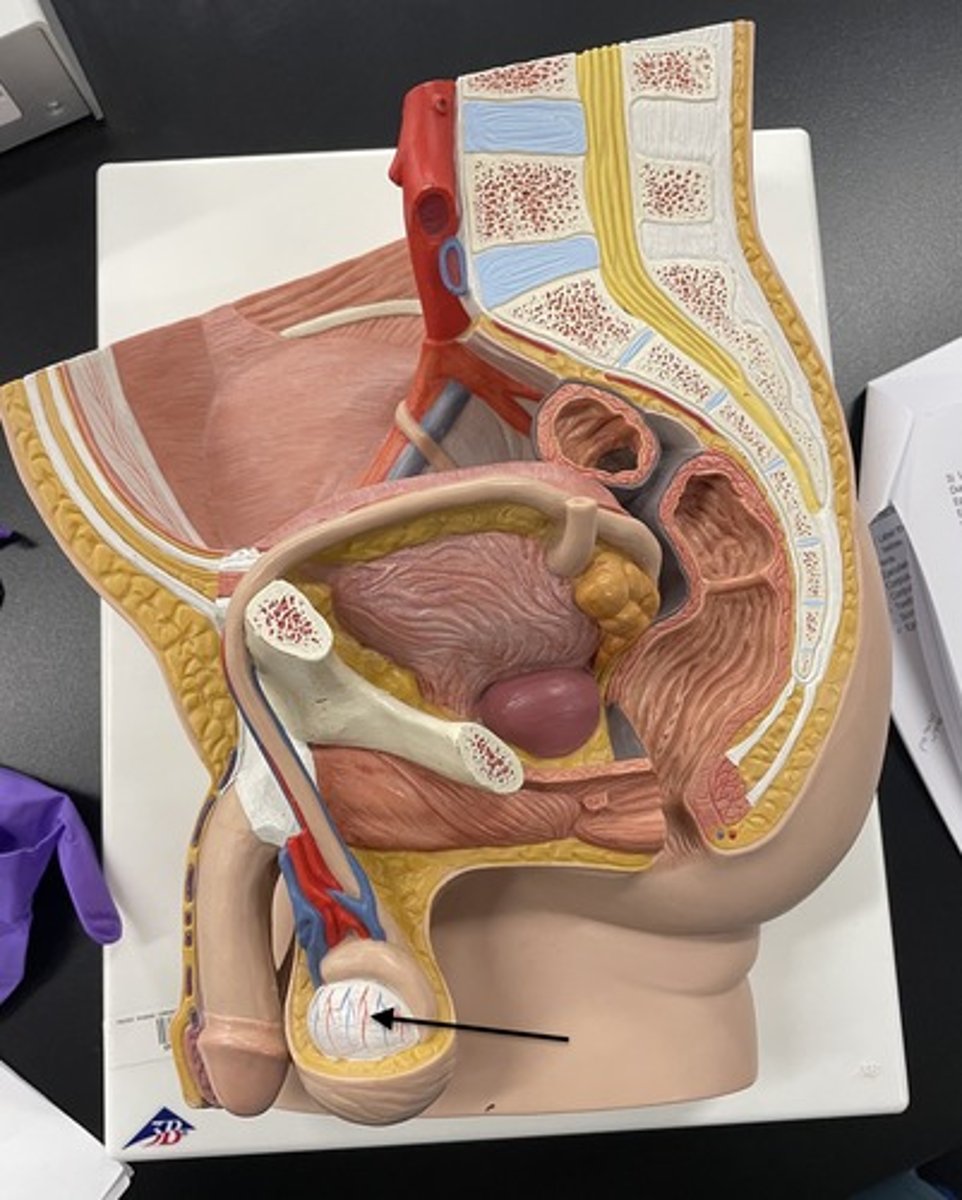

Scrotum

Testis (testes)

Epididymis

Epididymis

Head (epididymis)

Epididymis

Epididymis

Body (epididymis)

Tail (epididymis)

Spermatic cord

Ductus deferens

Prostate gland

Urethra

Penis

Erectile tissue

Corpus cavernosum

Corpus spongiosum